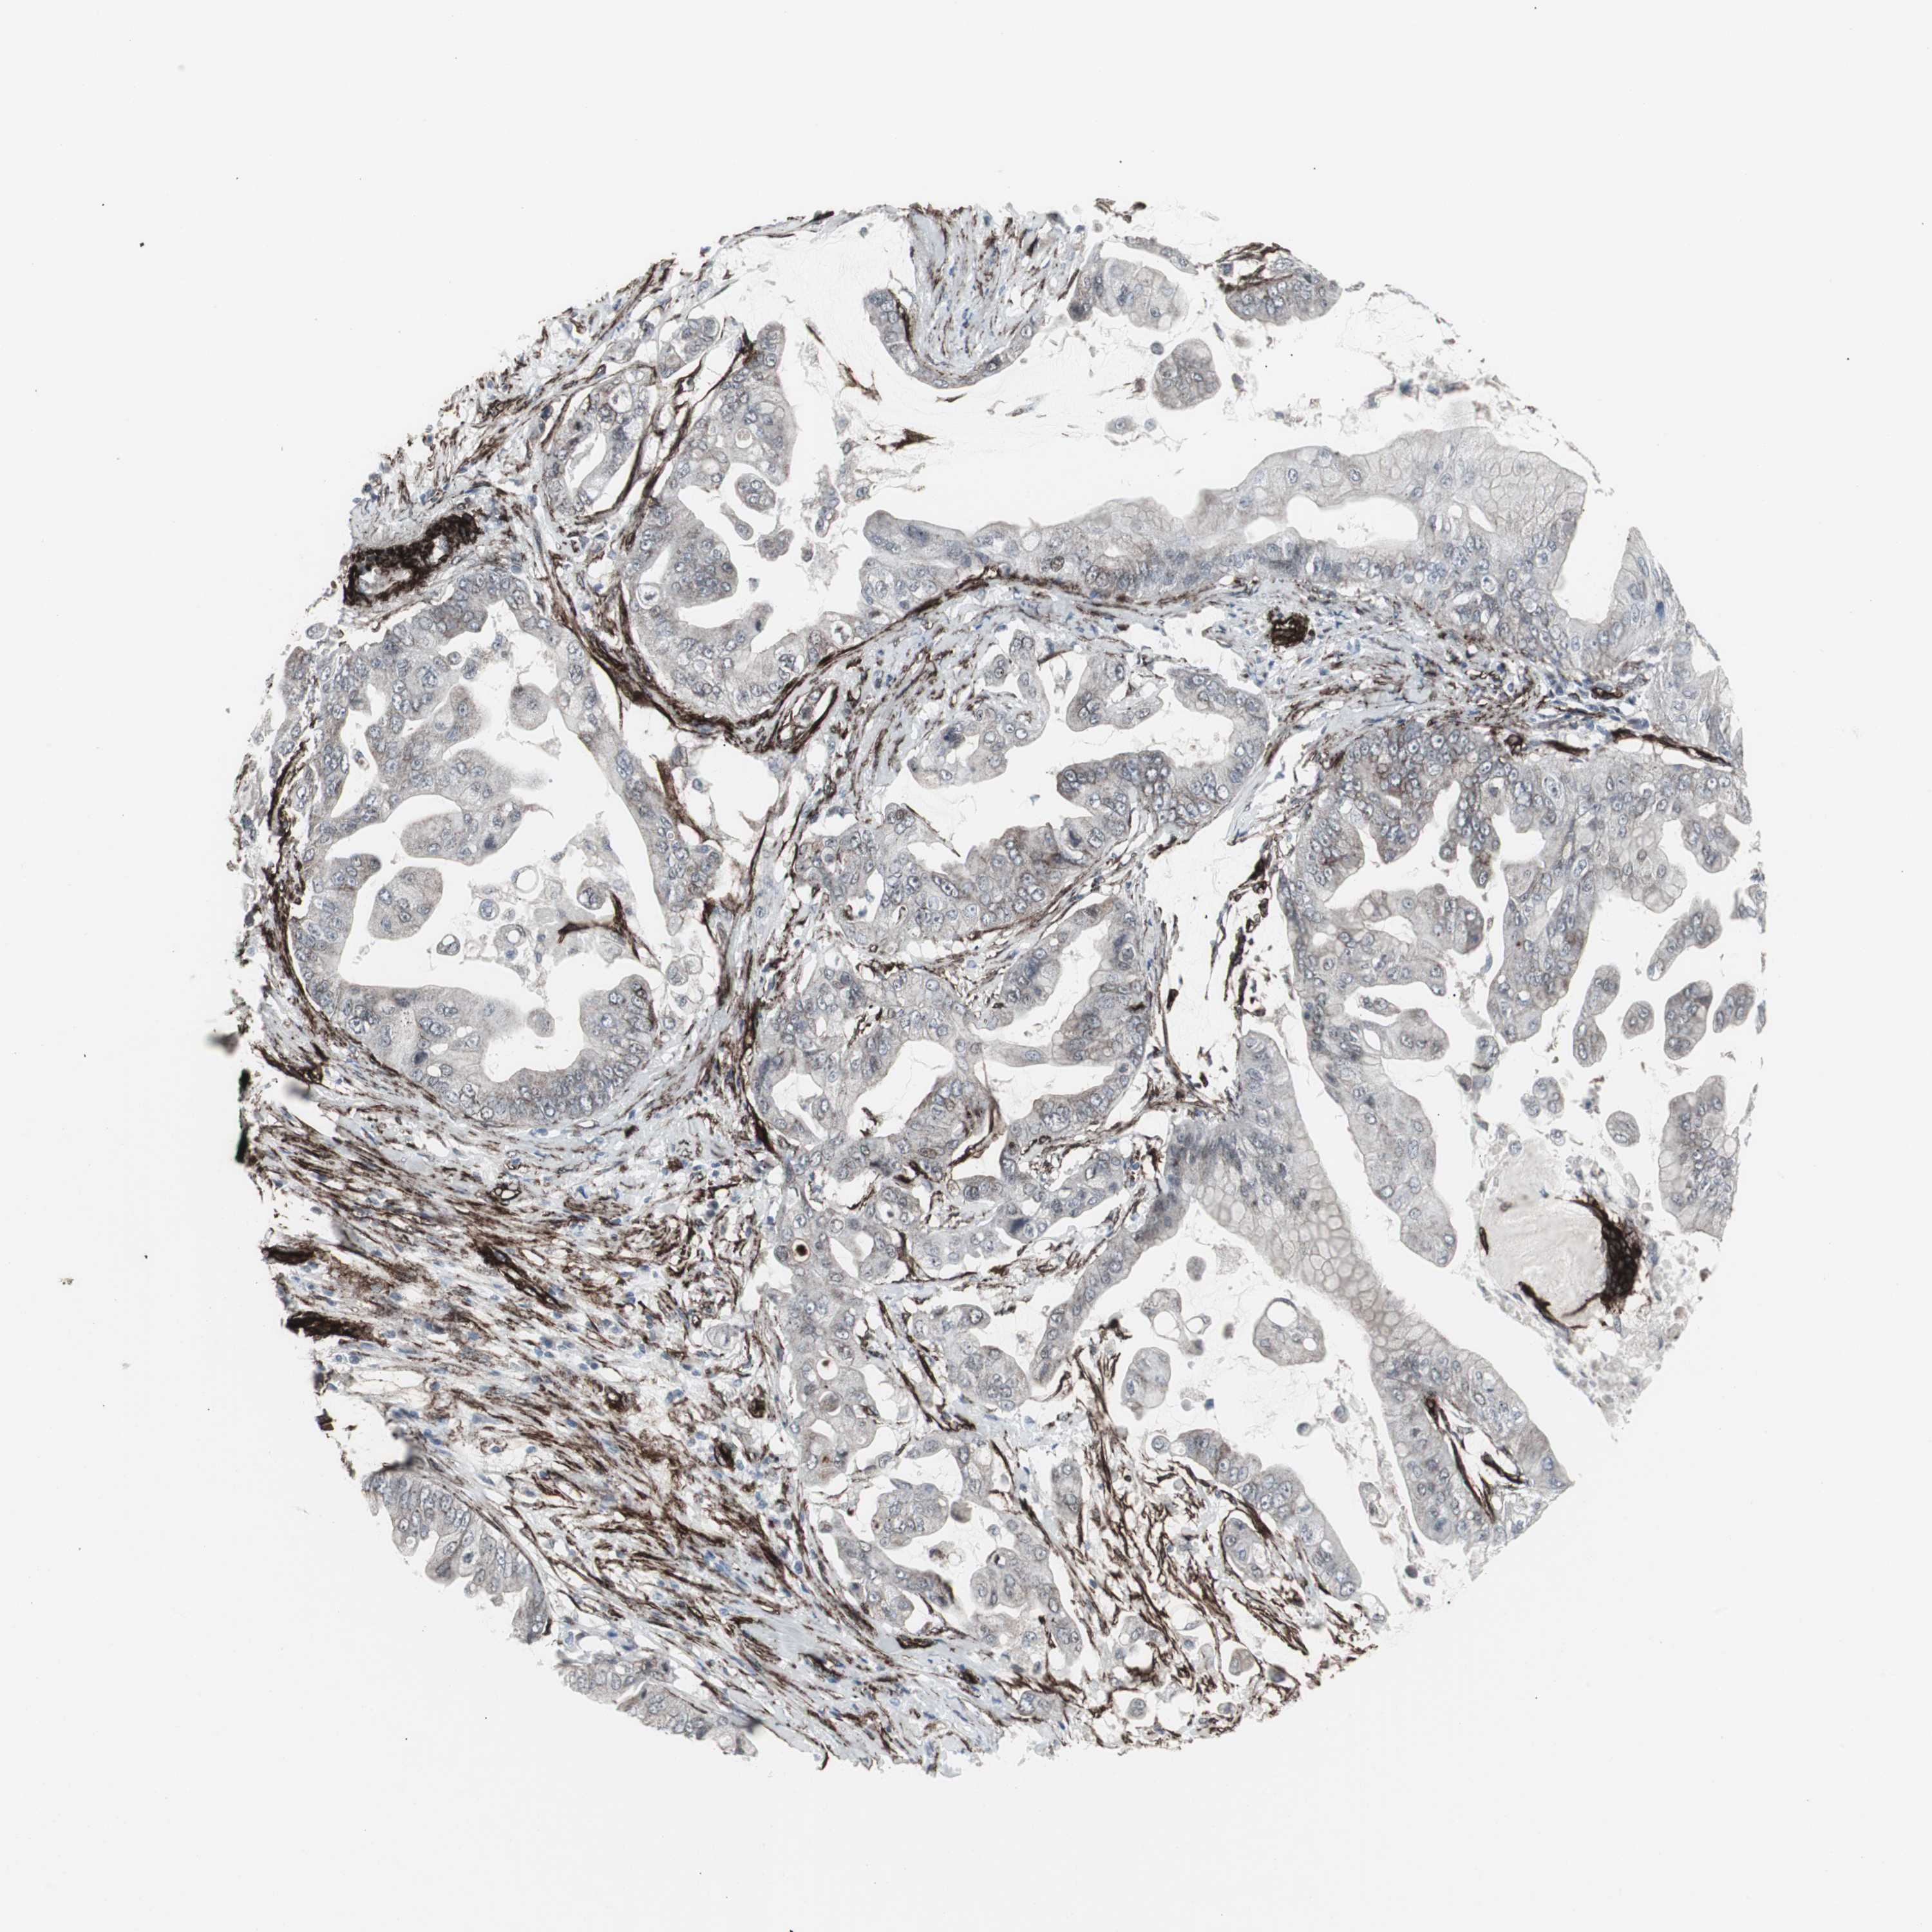

PANCREATIC CANCER - Protein expressioni

A mouse-over function shows sample information and annotation data. Click on an image to view it in a full screen mode. Samples can be filtered based on level of antibody staining by selecting one or several of the following categories: high, medium, low and not detected. The assay and annotation is described here.

Note that samples used for immunohistochemistry by the Human Protein Atlas do not correspond to samples in the TCGA dataset.

Antibody stainingi

Antibody staining in the annotated cell types in the current human tissue is reported as not detected, low, medium, or high, based on conventional immunohistochemistry profiling in selected tissues. This score is based on the combination of the staining intensity and fraction of stained cells.

Each image is clickable and will lead to virtual microscopy that enables deeper exploration of all samples and also displays staining intensity scores, fraction scores and subcellular localization as well as patient and tissue information for each sample.

Antibody CAB005579

Staining

High

Medium

Low

Not detected

Intensity

Strong

Moderate

Weak

Negative

Quantity

>75%

75%-25%

<25%

None

Location

Nuclear

Cytoplasmic/membranous

Cytoplasmic/membranous,nuclear

Adenocarcinoma, NOS

Adenocarcinoma, metastatic, NOS